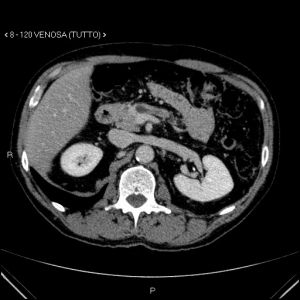

Aspetti TC: piccolo nodulo istmico ipervascolarizzato in fase pancreatica

Aspetti TC: piccolo nodulo istmico iperdenso in fase venosa.